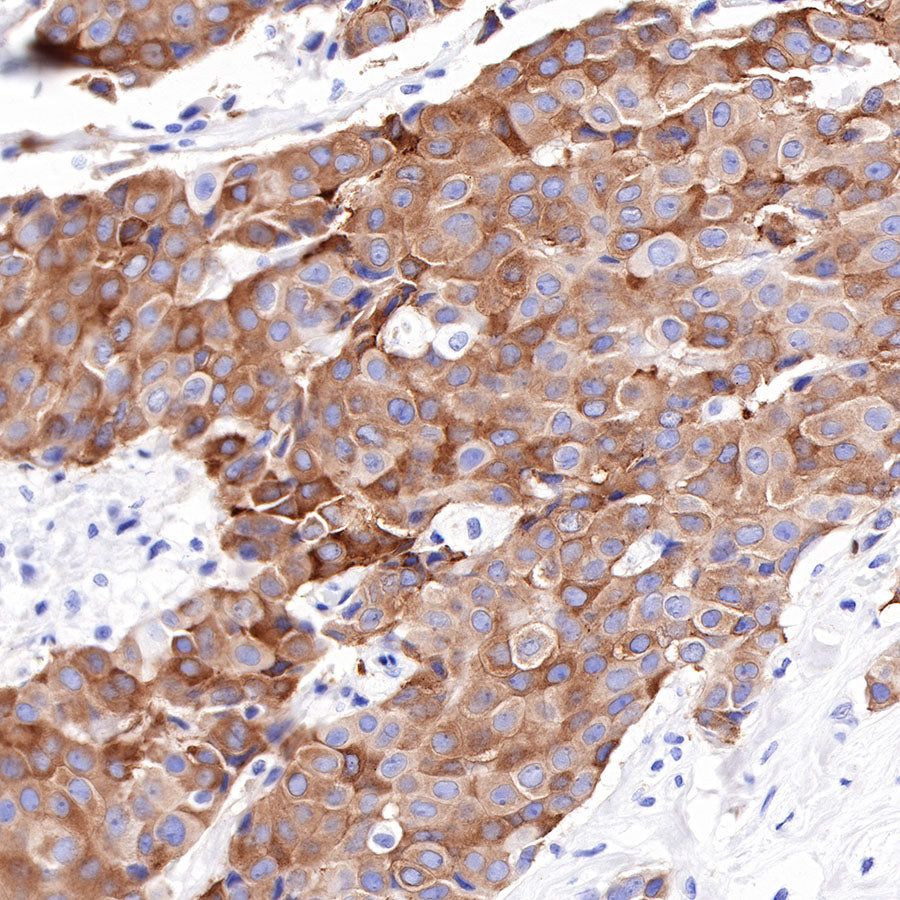

Immunohistochemistry

IHC shows positive staining in paraffin-embedded human breast cancer. Anti-Tau antibody was used at 1/2000 dilution, followed by a HRP Polymer for Mouse & Rabbit IgG (ready to use). Counterstained with hematoxylin. Heat mediated antigen retrieval with Tris/EDTA buffer pH9.0 was performed before commencing with IHC staining protocol.